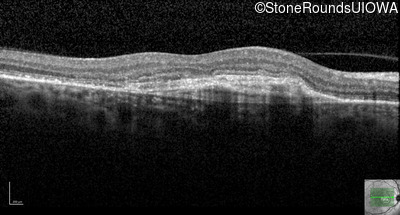

Age at visit: 59 years (Visit 3)